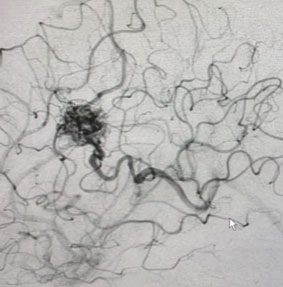

Angiogram (Figure 3 and 4) confirmed the presence of a deep left frontal AVM without any associated aneurysms.

Fig. 3

Fig. 4